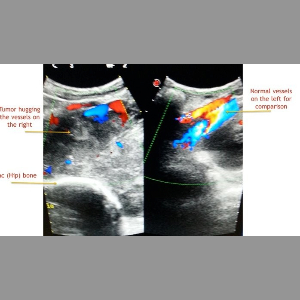

Do not neglect leg swelling!

Lets you know about a dangerous cause for leg swelling!

Do not neglect leg swelling!

Lets you know about a dangerous cause for leg swelling!